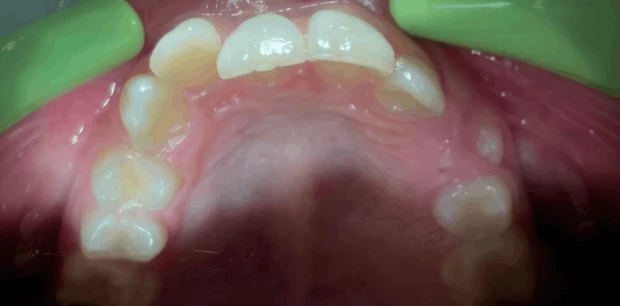

Ортодонтия

Исправление прикуса и выравнивание зубов брекет-системой

Пациент У., 15 лет. Родители обратились с жалобами на неровные зубы сына. Проведено ортодонтическое лечение брекет-системами. Лечение проводилось 2 года.